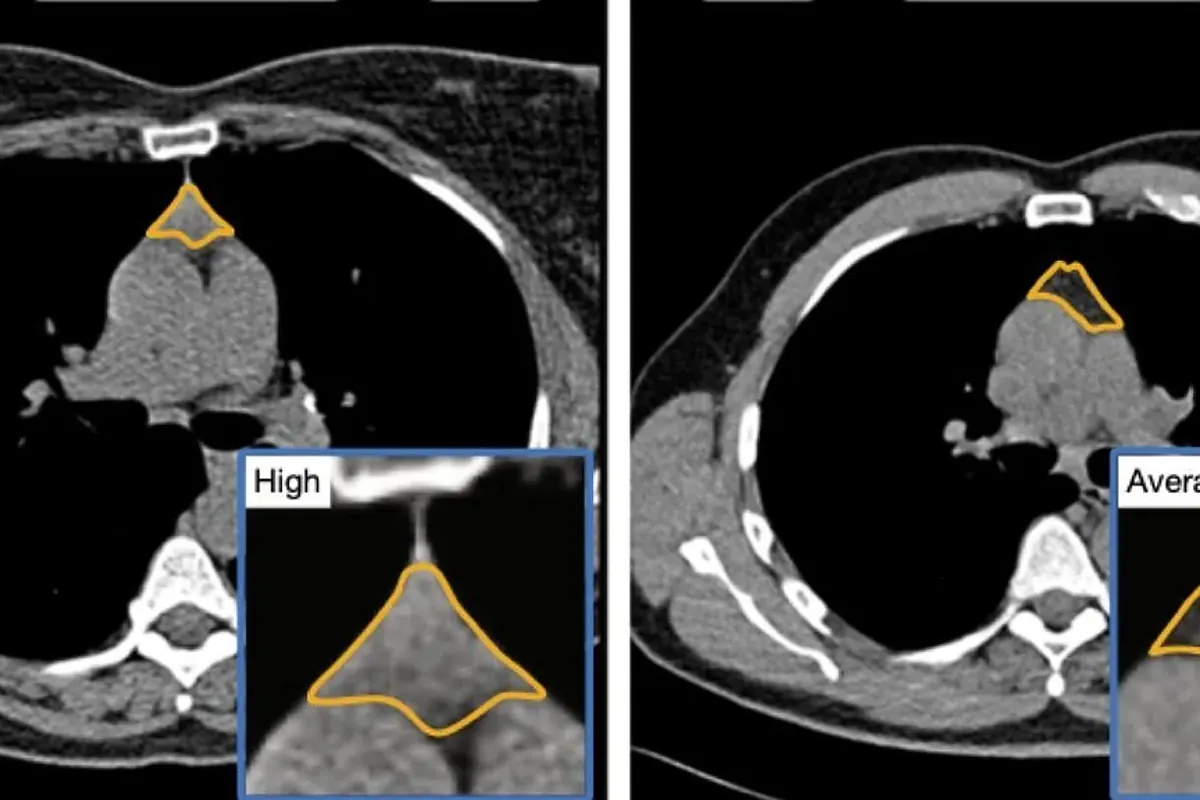

Nuevos estudios de investigadores del Mass General Brigham revelan que el timo, órgano olvidado tras la pubertad, es crucial para prevenir el cáncer y la salud cardiovascular en adultos...